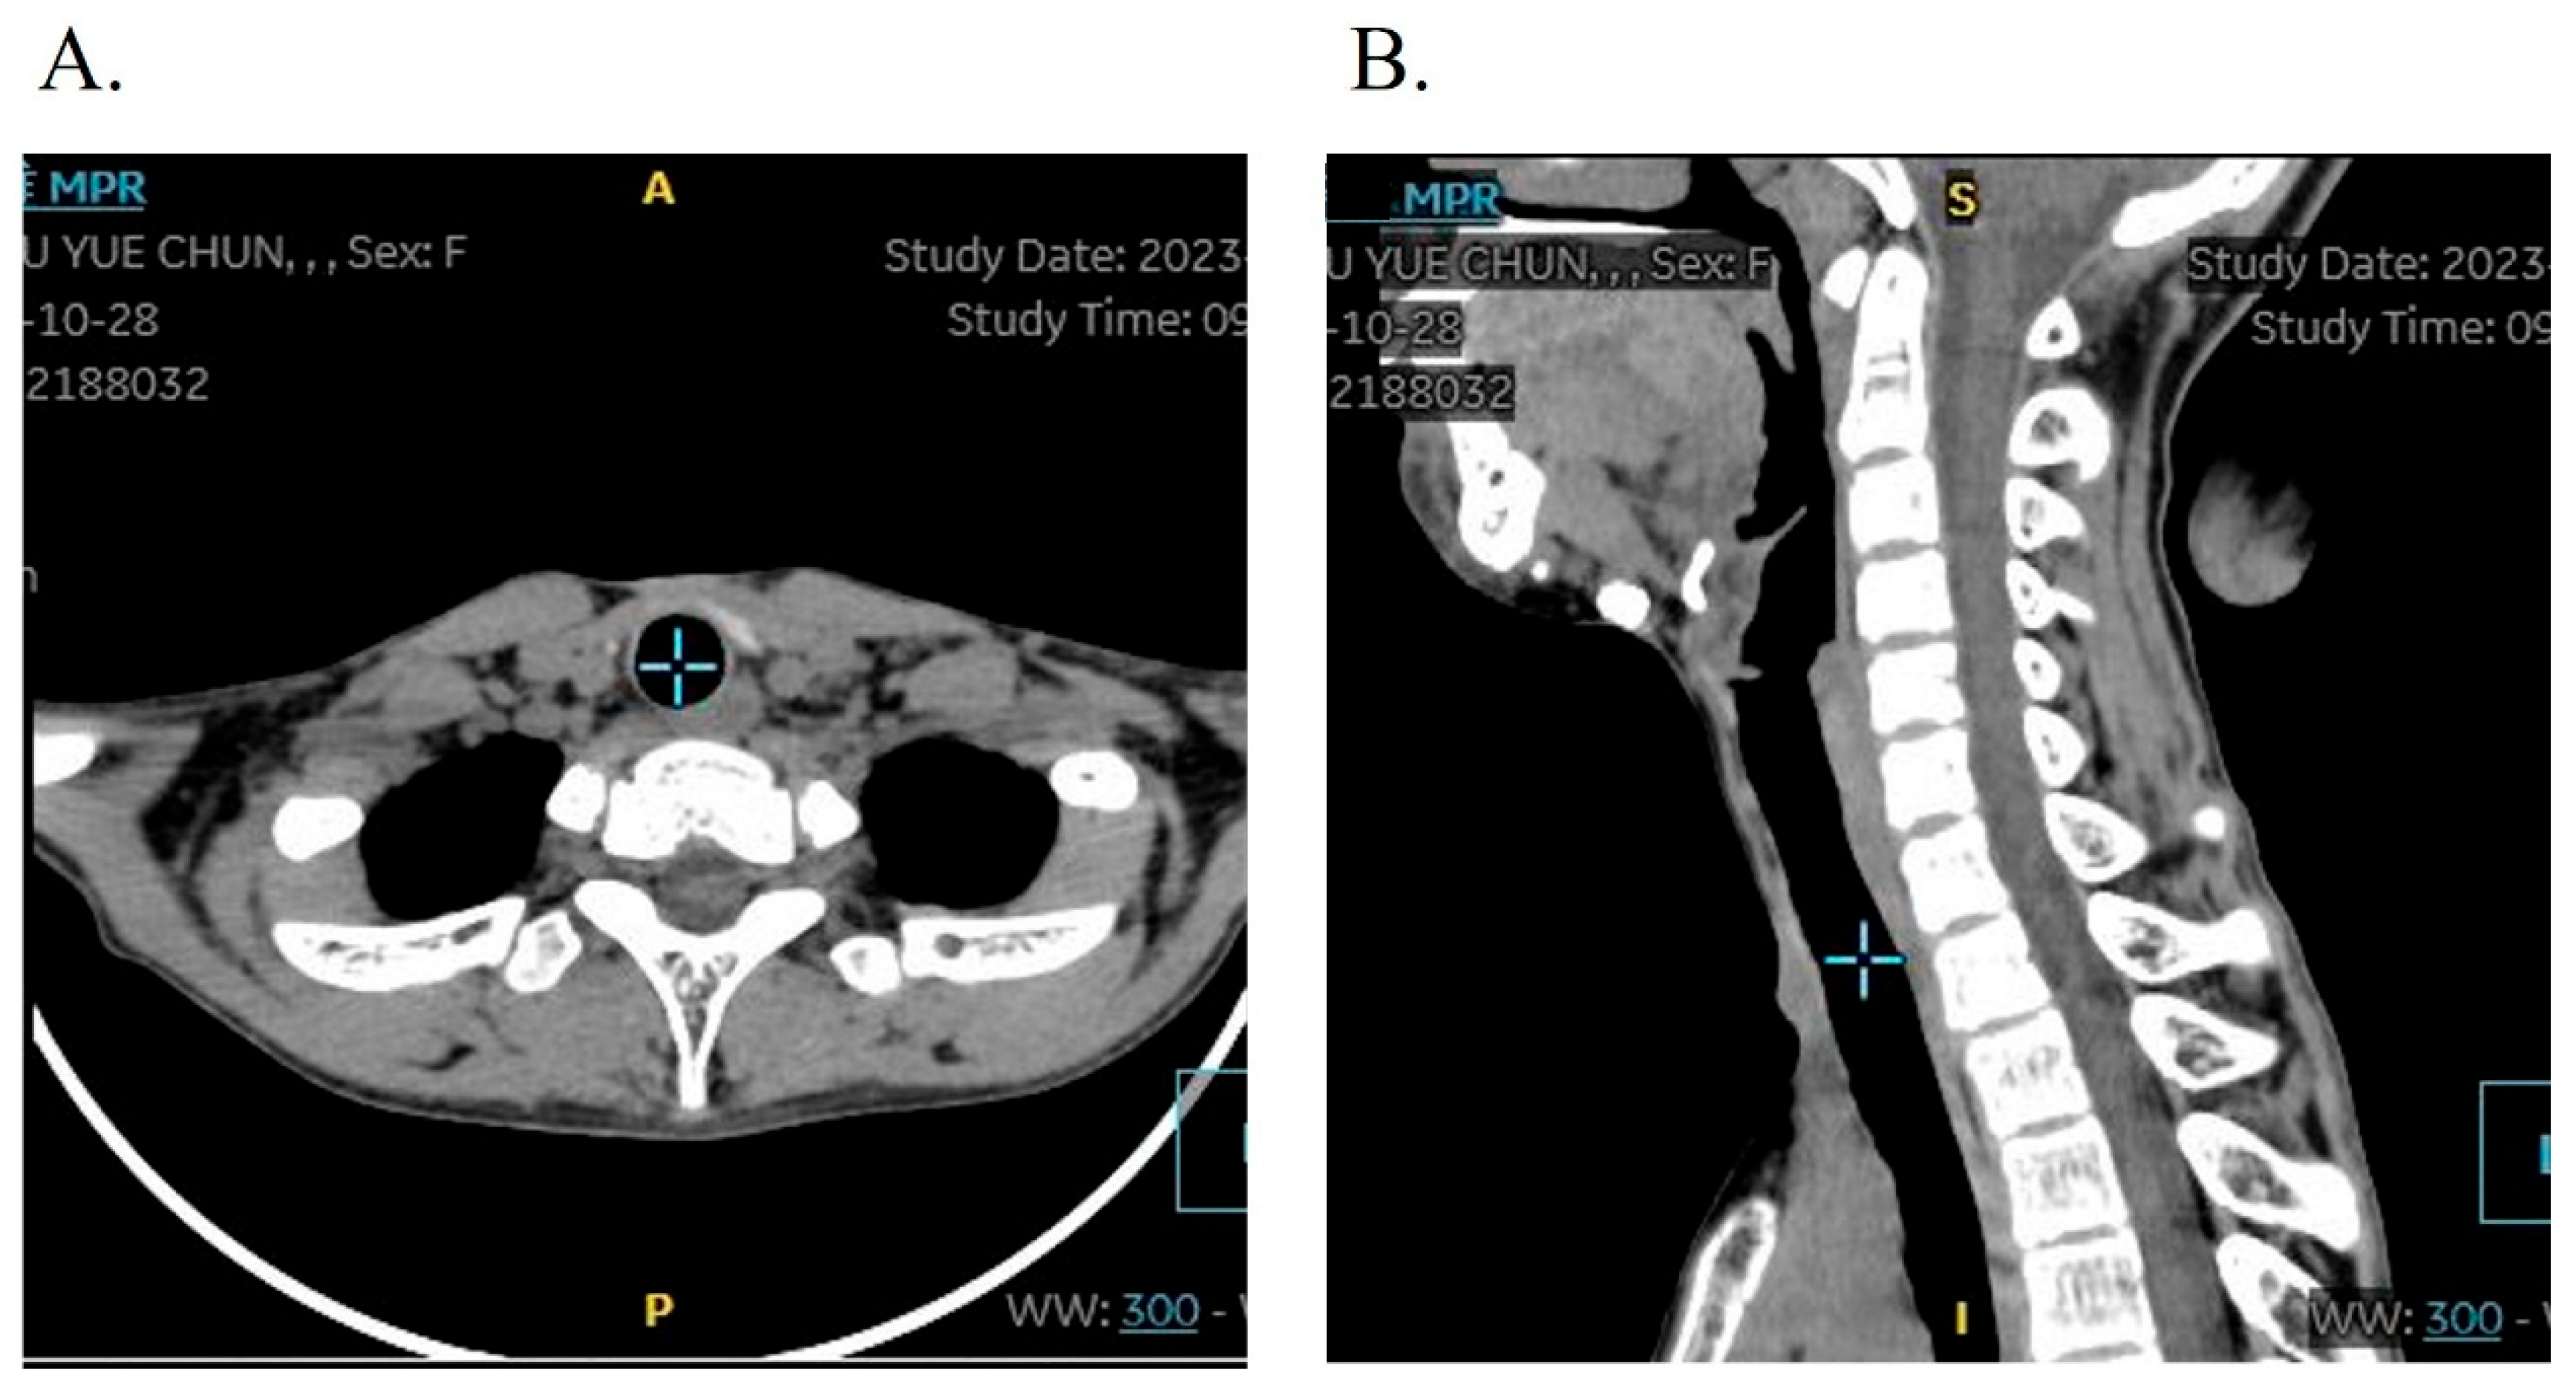

Tracheotomy-associated complications were observed in three patients (8.57%, 3/35), comprising incision site tissue hyperplasia in all three cases (8.57%) and tracheal stenosis in one case (2.86%) who presented with mild tracheal softening and stenosis, demonstrating difficulty in decannulation after tracheostomy. A T-tube was implanted via electronic bronchoscopy, with postoperative follow-up confirming restoration of normal respiratory function and voice production. The follow-up CT showed a normal trachea structure without airway stenosis. Crucially, all patients underwent uneventful decannulation, with no instances of severe complications such as wound dehiscence or respiratory infections. Follow-up CT showed no obvious structural changes in the tracheal lumens (Figure 5).

Figure 5. Follow-up CT of the tracheal tract in axial view (A) and sagittal view (B). There are no obvious structural changes to the trachea lumens.